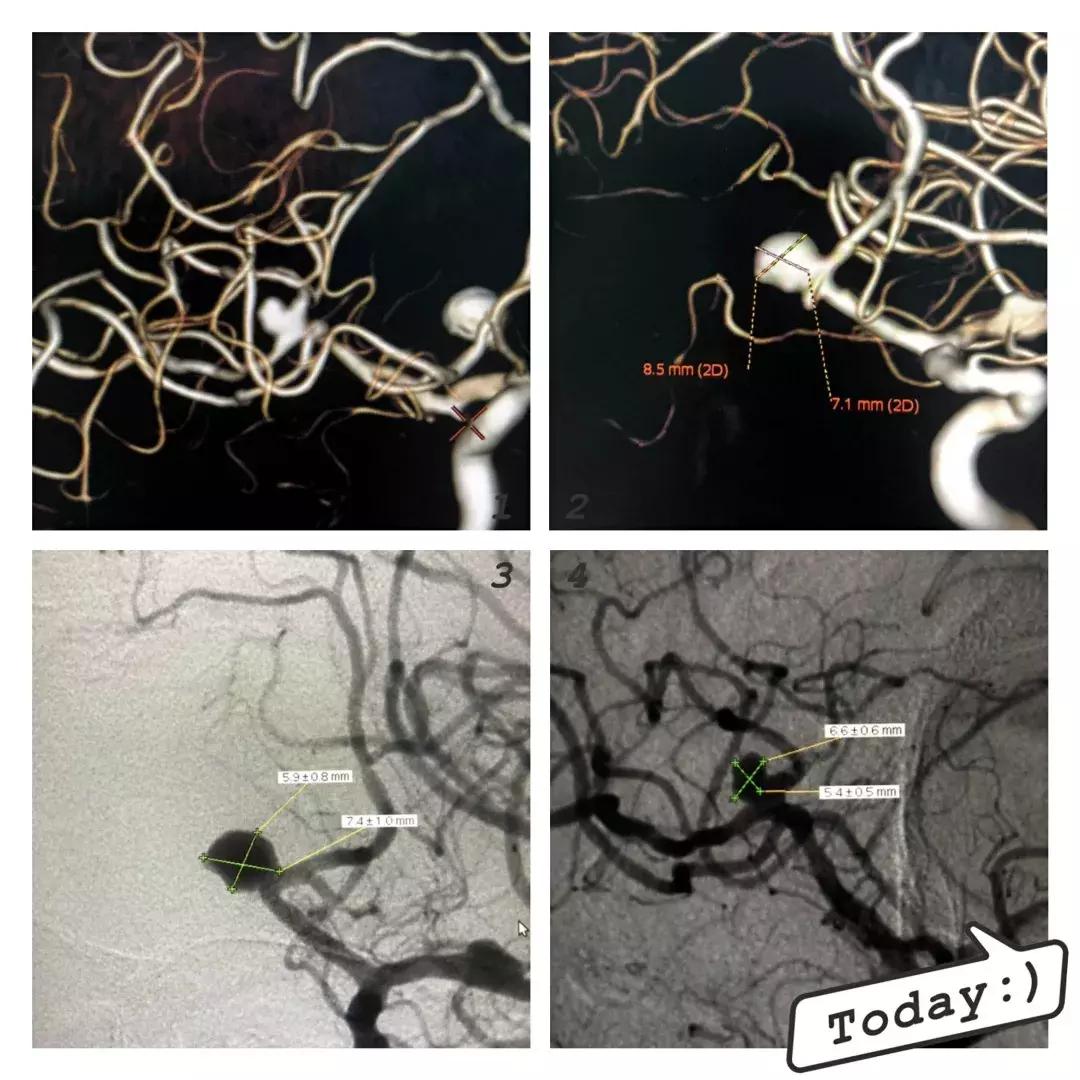

6月27日行全脑血管造影进一步证实:左侧大脑中动脉上下干分叉处动脉瘤;右侧大脑中动脉M1M2交界处动脉瘤;右侧大脑前动脉前交通处动脉瘤。

左侧大脑前动脉前交通动脉瘤,瘤颈8.1mm,瘤体8.1mmx3.3mm,右侧大脑中动脉上下干分叉处动脉瘤,瘤颈5.1mm,瘤体5.1mmx4.7mm毫米。均在路图导引下,经支架导管引入支架至动脉瘤颈处,支架半释放,在导丝配合下,将微导管送入动脉瘤腔内,撤出微导丝,依次填塞弹簧圈至瘤腔腔内,完全释放支架,术后反复造影,提示动脉瘤栓塞致密,无造影剂滞留。该次手术一次性解决了两个瘤体破裂的风险!